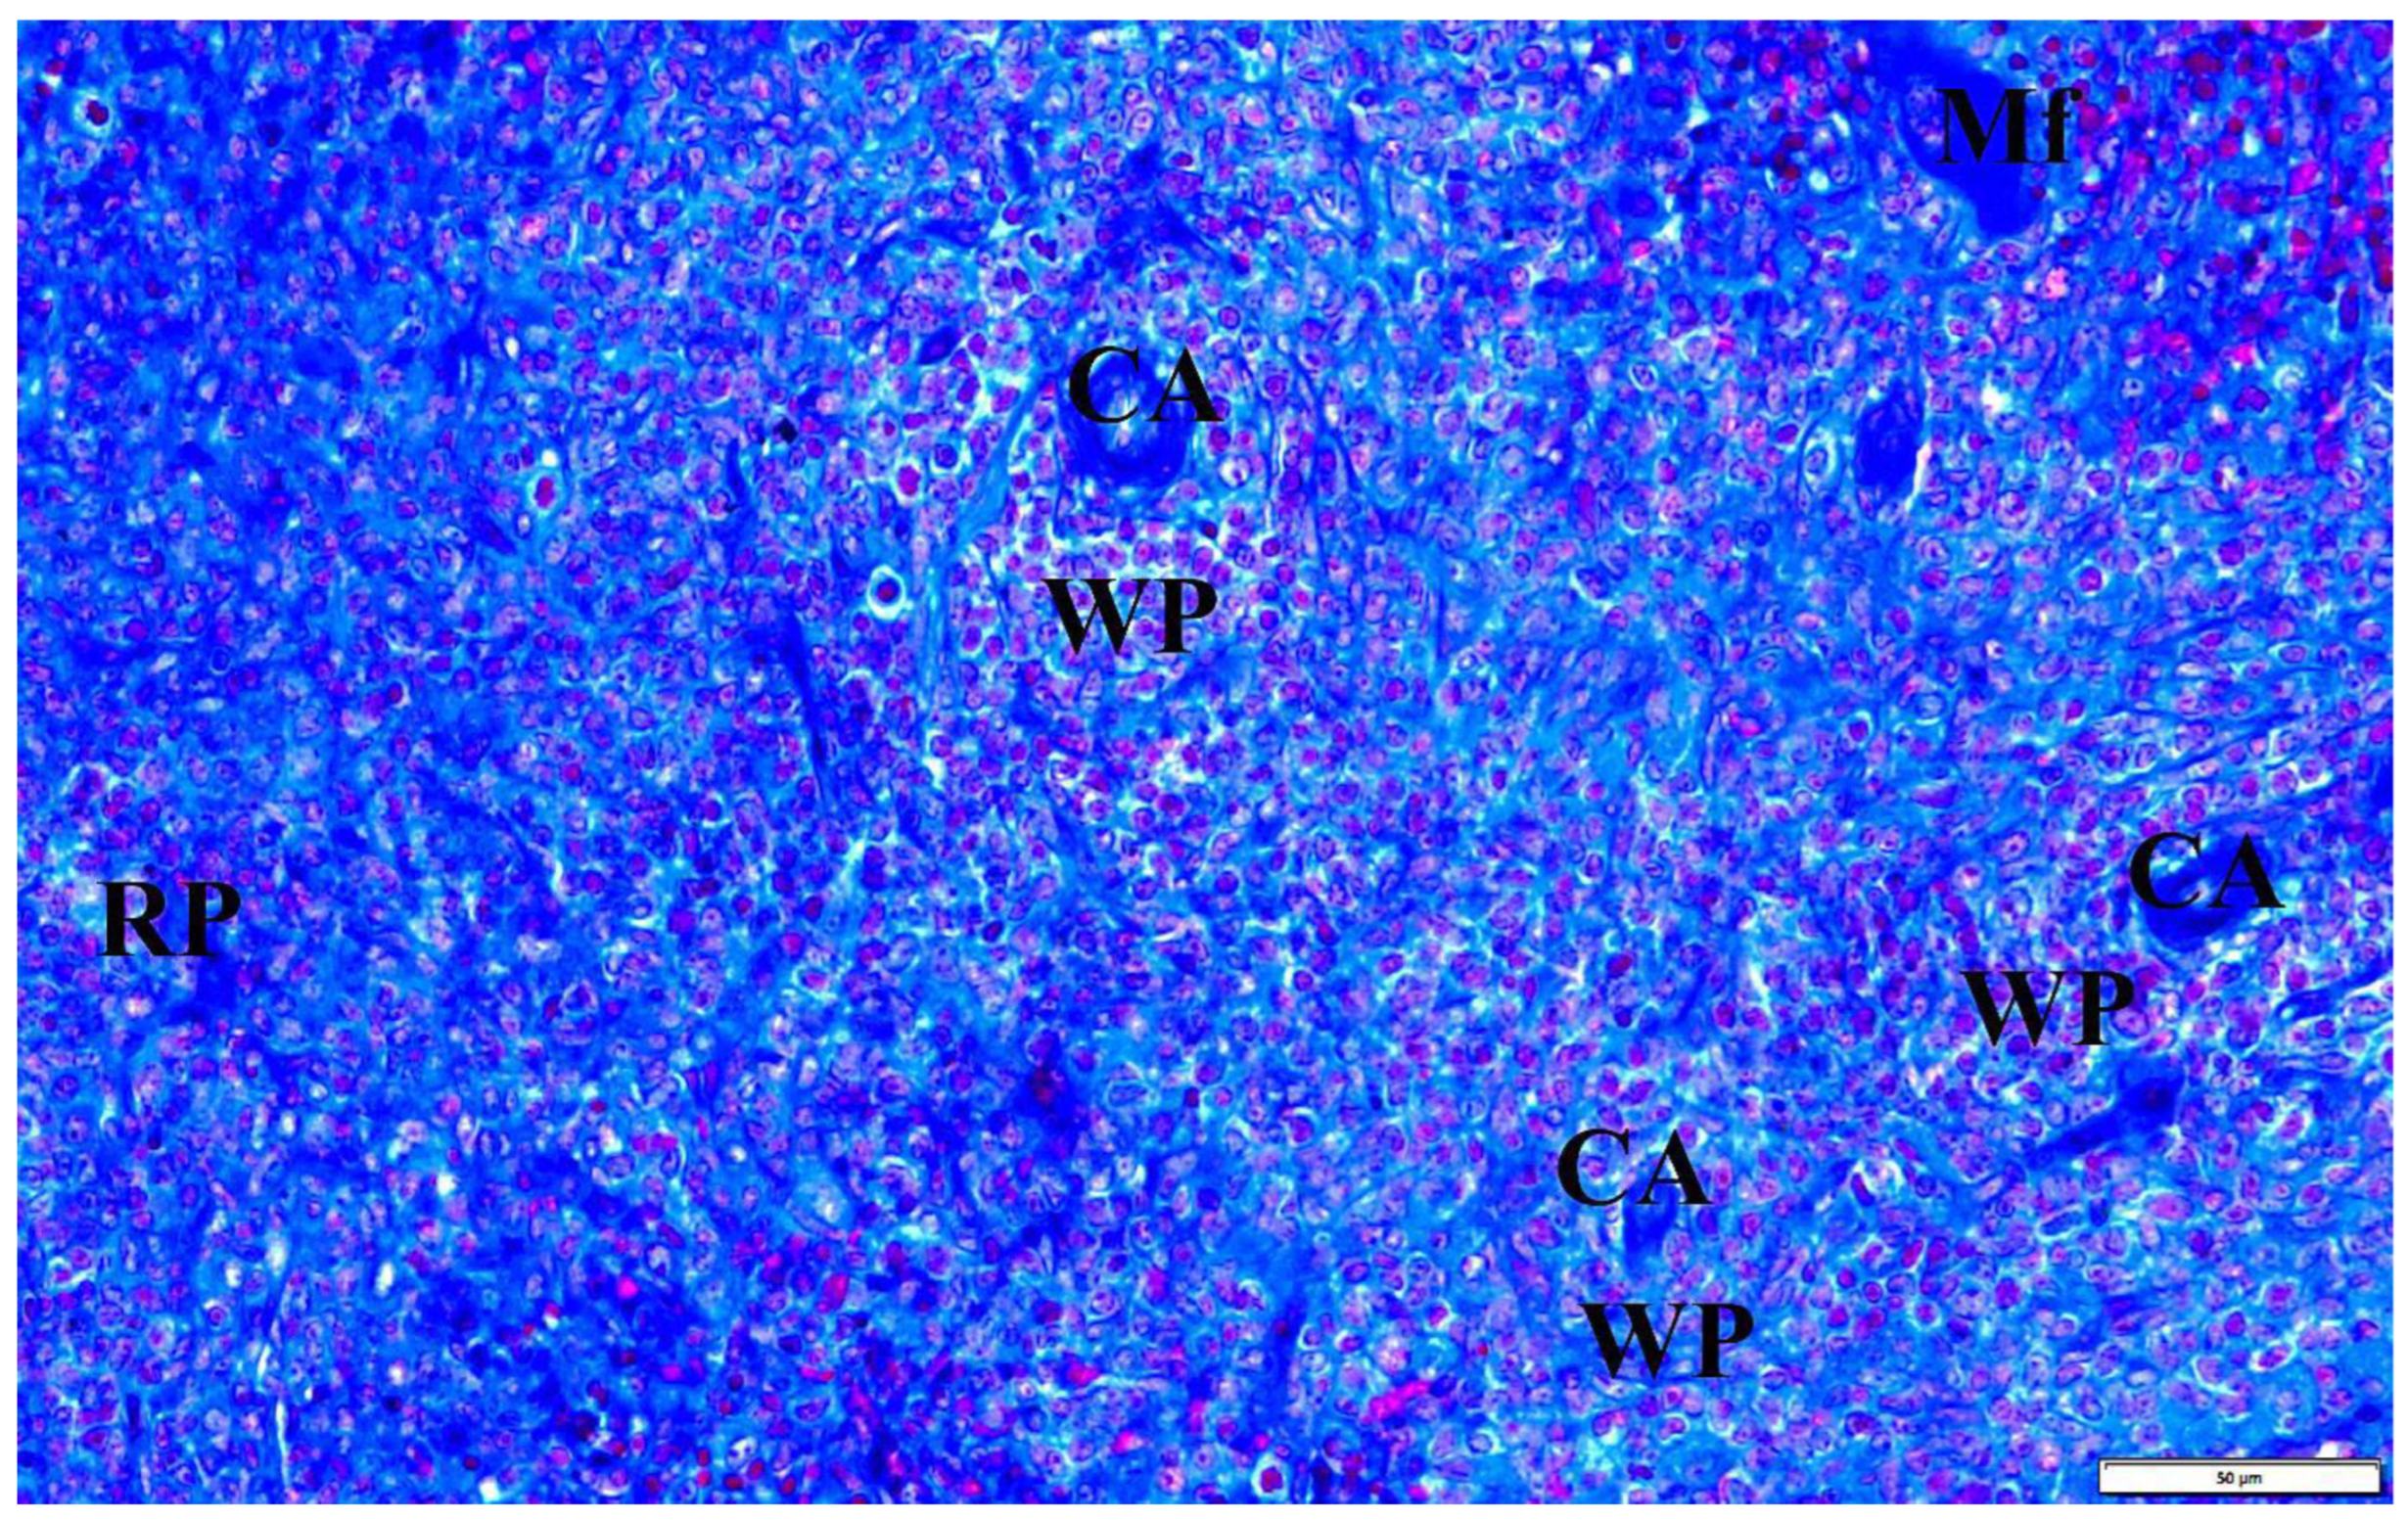

In the presented studies, in the histological structure of the spleen of intrauterine infected rats with B. microti, no clear deviations from the normal architecture of the organ were observed, appropriate to the young age of the observed individuals. Both white and red pulp were visible. However, the line between them was blurred (Figure 8). The lymphoid follicles were irregular in shape and the marginal layer was barely perceptible. The fibrous capsule of the spleen of rats under physiological conditions is characterized by a small amount of connective tissue. In the observed preparations of spleen sections taken from rats with congenital babesiosis, a small amount of it was visible with the presence of mesothelial cells covering its surface. The connective tissue capsule detached from the parenchyma of the organ in places, creating fissured spaces. These dissections indicate degenerative changes, possibly associated with edema. The trabeculae extending from the splenic capsule were visible and contained vessels with fibrin-precipitated hyperemia and numerous blood cells adhering to the endothelial wall (Figure 9). In addition, a characteristic feature was the differentiation of erythrocytes.

Figure 8.

The spleen of a rat with transplacental infection with B. microti 3 weeks after birth. CA—central artery, Mf—macrophage, WP—lymphoid follicles (white pulp), RP—red pulp.